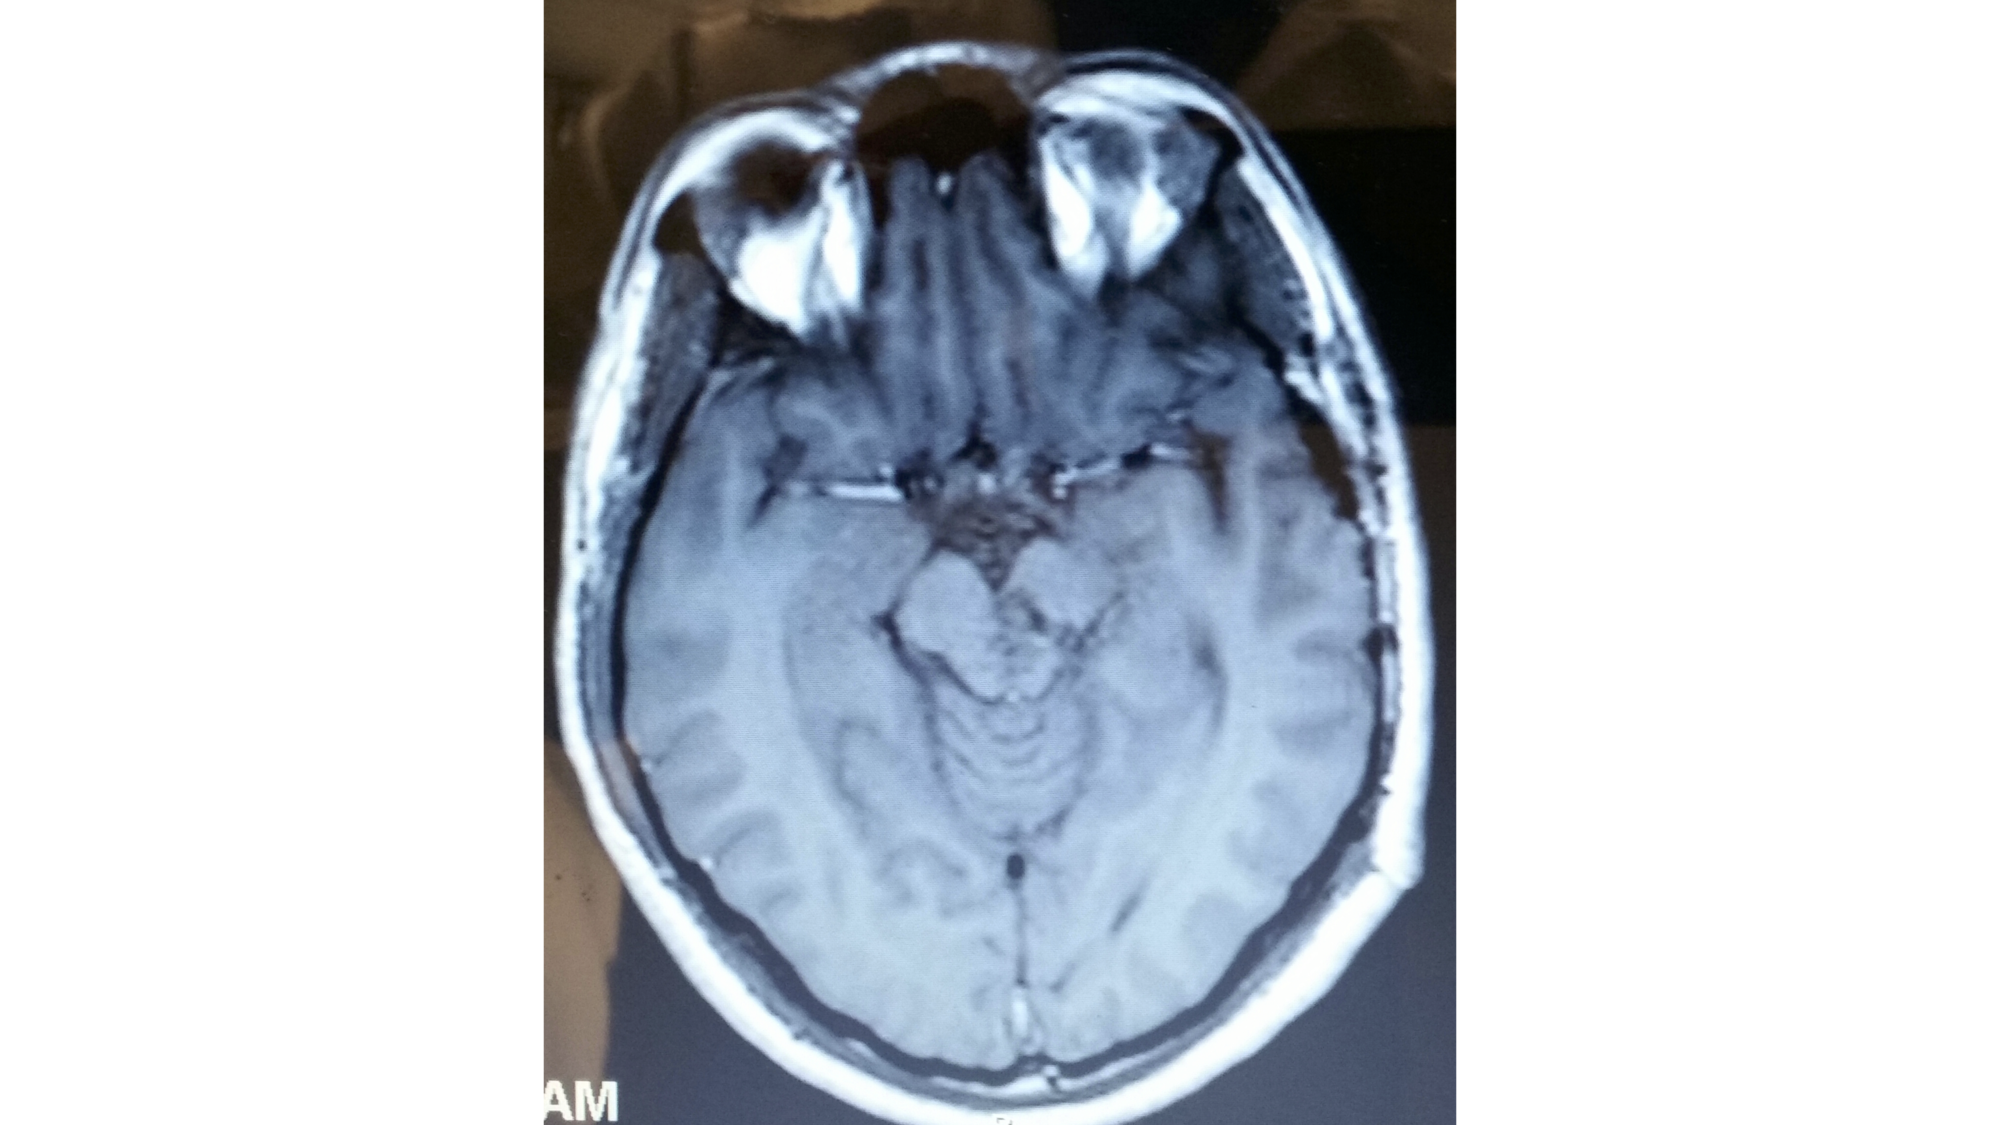

An 18-year-old male presented in 2009 with a six-year history of repeated hemorrhage from a brainstem cavernous malformation (Figure 5).

At his most recent presentation, he developed repeated episodes of temporary right hemiparesis and decreased fluency of speech. The lesion was removed via a lateral brain stem approach. The brain stem was opened using the midbrain entry site along the posterior half of the incision shown in Figure 4. The postoperative magnetic resonance imaging (MRI) of the case illustration is shown in Figure 6.